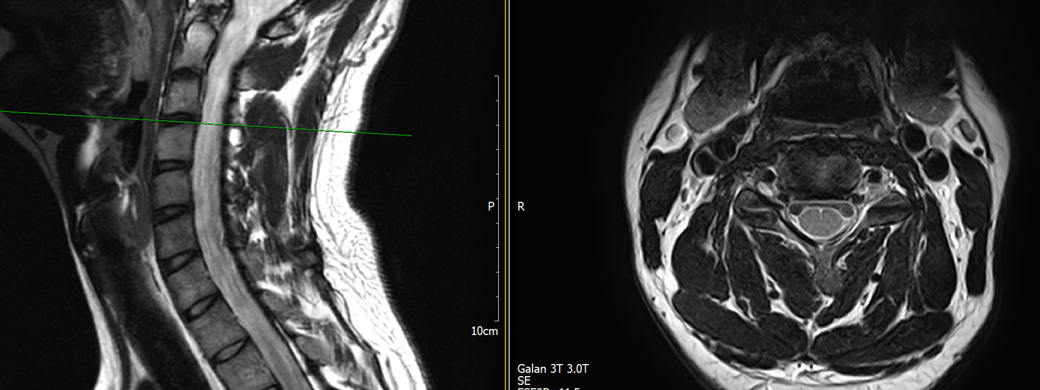

목과 오른쪽 어께 통증이 있어 mri를 찍어왔는데, 사진에서 의심되는 부분 있을까요?

• 4번 째 사진

MRI만 보면 굉장히 깨끗한 목입니다.

디스크탈출은 없고 신경뿌리가 압박될만한 모습도 전혀 보이지 않습니다.

지금은 MRI에서 잘 보이지 않는 디스크내장증일 가능성이 높아보이며 경추전만 자세를 잘 유지해주시는게 가장 큰 도움이 되겟습니다.